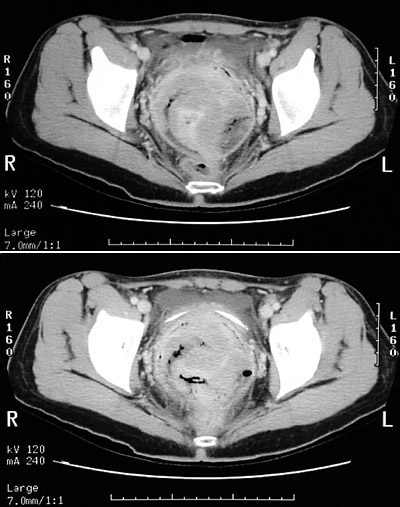

![]() | These abdominal CT scan views of the pelvis demonstrate a large mass with necrosis and air-filled spaces arising in the cervix and extending anteriorly to the bladder and posteriorly to the rectum. This is a squamous cell carcinoma of the cervix that has invaded both rectum and bladder--stage IV. |